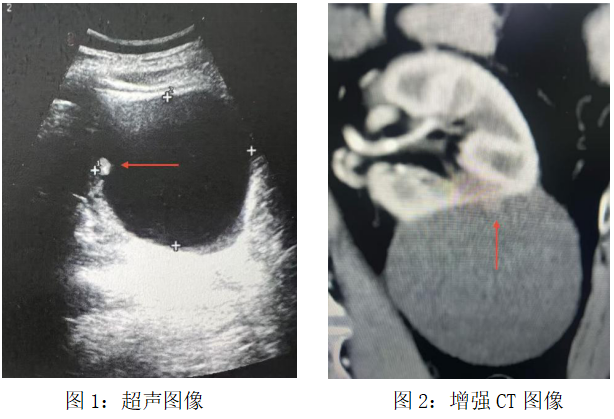

直到超声医生的探头停留在某个细微处:囊肿内壁上,一个仅7毫米大小的实性结节,如同沉睡的火山,暗示着平静表面下的汹涌。这是一位老年男性的体检报告,却成了北京大学首钢医院泌尿肿瘤MDT团队接到的“集结令”。

“这个囊肿不单纯,警惕恶性肿瘤风险,需要做个增强 CT 确认一下。”超声科医生的判断拉响了第一声警铃。常规体检报告上的“肾囊肿”本是临床上常见良性病症,可这枚比指甲盖还小的结节,却像一个持续闪烁的红色警报,在超声医生心里不断回响。

增强CT的结果证实了担忧:Bosniak Ⅳ级复杂肾囊肿,恶性概率极大。所谓复杂肾囊肿是指囊肿存在囊壁增厚、分隔、钙化、实性结节等情况,如同裹着糖衣的“定时炸弹”,必须尽快启动专科诊疗。